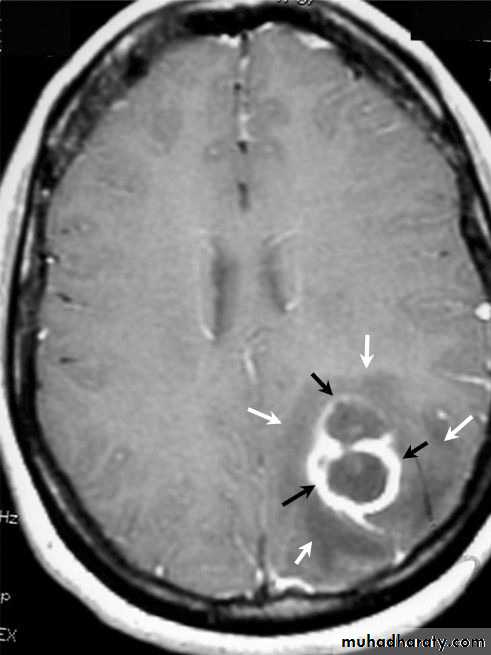

• B. Radiological Investigations:• CT or MRI is the investigation of choice.

• CT Brain is performed with and without contrast.

• MRI is done with gadolinium enhancement.

• They will show a single (or multiple) space occupying lesion that is well delineated with an enhancing wall, with variable surrounding oedema.

Brain Abscess MRI

Multiple Abscesses